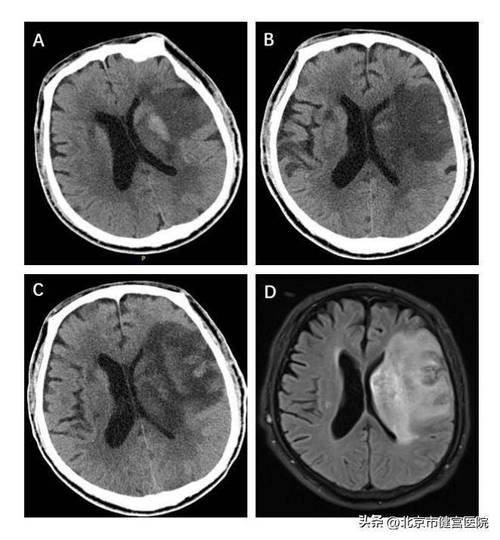

急性期(6小时 - 3天):

- 密度降低(最典型表现):坏死的脑组织因为细胞水肿和坏死,密度会逐渐降低,在CT图像上表现为低密度灶,这个区域通常呈楔形,其尖端指向血管的走向。

- 占位效应:随着水肿加重,梗死区域周围的脑组织会被挤压,导致中线结构(如大脑镰)移位,脑室受压变形。

亚急性及慢性期(3天以后):

- 边界更清晰:低密度灶会变得更加清楚、锐利。

- 脑萎缩:长期后,坏死的脑组织会被吸收,形成囊腔,局部脑组织会萎缩,表现为脑沟加深、脑室扩大。